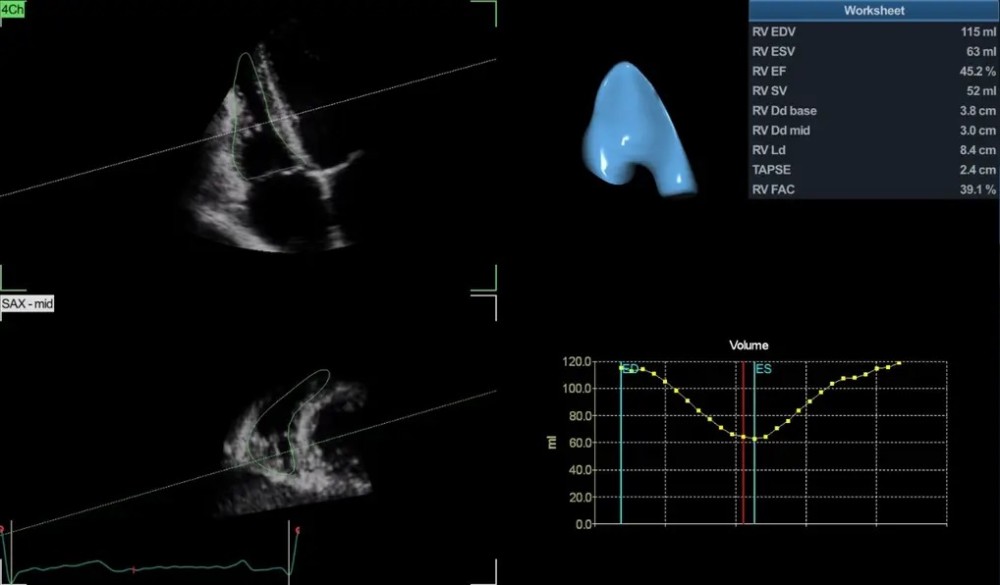

4D Auto LVQ — sol ventrikulun 4D avtomatik kvantitativ analizi

GE Vivid S70N Dimension — mütəxəssis kardiologiyası üçün nəzərdə tutulmuş inkişaf etmiş ultrasəs sistemi. Bu model təkmilləşdirilmiş 4D ekokardioqrafiya funksiyalarına malikdir və matriks  (TEE) problarını dəstəkləyir. Sistem həmçinin kvantitativ həcmli məlumatların təhlili və qiymətləndirilməsi üçün geniş alətlər toplusunu təmin edir.

cSound platforması əsasında işləyən Vivid S70N Dimension ürək və damar strukturlarının yüksək dəqiqlikli görüntülənməsini təmin edir, beləliklə kardiologiya üzrə mütəxəssis mərkəzlər, funksional diaqnostika şöbələri və yüksək diaqnostik dəqiqlik tələb edən tibb müəssisələri üçün ideal seçimdir.